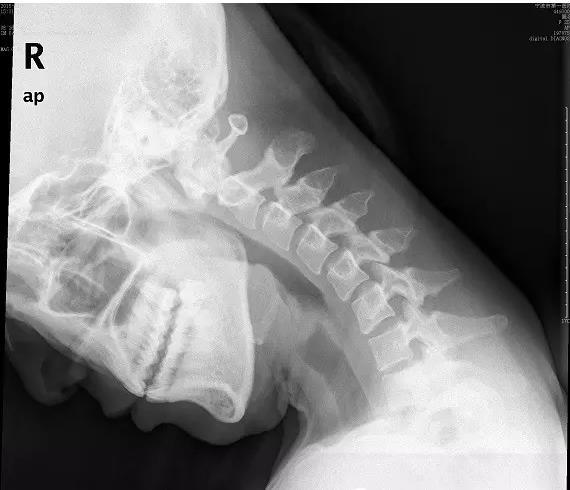

近日门诊接诊了一位18岁的花季少女小美,说是颈部疼痛难忍,已经半个月了,实在疼的不行了才来医院看看。拍片后显示:颈椎退变,生理弧度消失、变直。下面这张就是小张的颈椎侧位片。片子上,颈椎排列略呈“S”形。而不象是正常的“C”形。